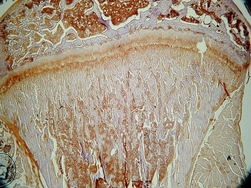

Õpiobjekt on osa Tartu Ülikoolis õpetatavast ainest Histoloogia, mis kuulub arstiteaduskonna õppekava kohustuslike erialaainete hulka nii ravi kui ka stomatoloogia erialal. Õpiobjektis antakse ülevaade histoloogias enim kasutatavatest uurimismeetoditest. Põhjalikumalt kirjeldatakse uurimismaterjali histoloogilise töötlemise etappe valgusmikroskoopia puhul, sealhulgas lõikude värvimist hematoksüliini ja eosiiniga.